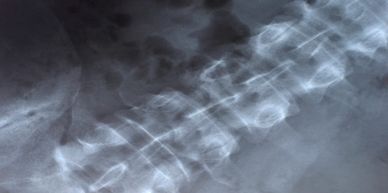

Chiropractic Medicine is a distinct, integrative healthcare field and science concerned with the relationship between the musculoskeletal and nervous system and the effects on the restoration and maintenance of physical health primarily when the body has been compromised. Specific techniques and protocols are integral

to reducing or eliminating symptoms, health restoration, and positive effects on mental health. "Adjustments" are the cornerstone in this field.